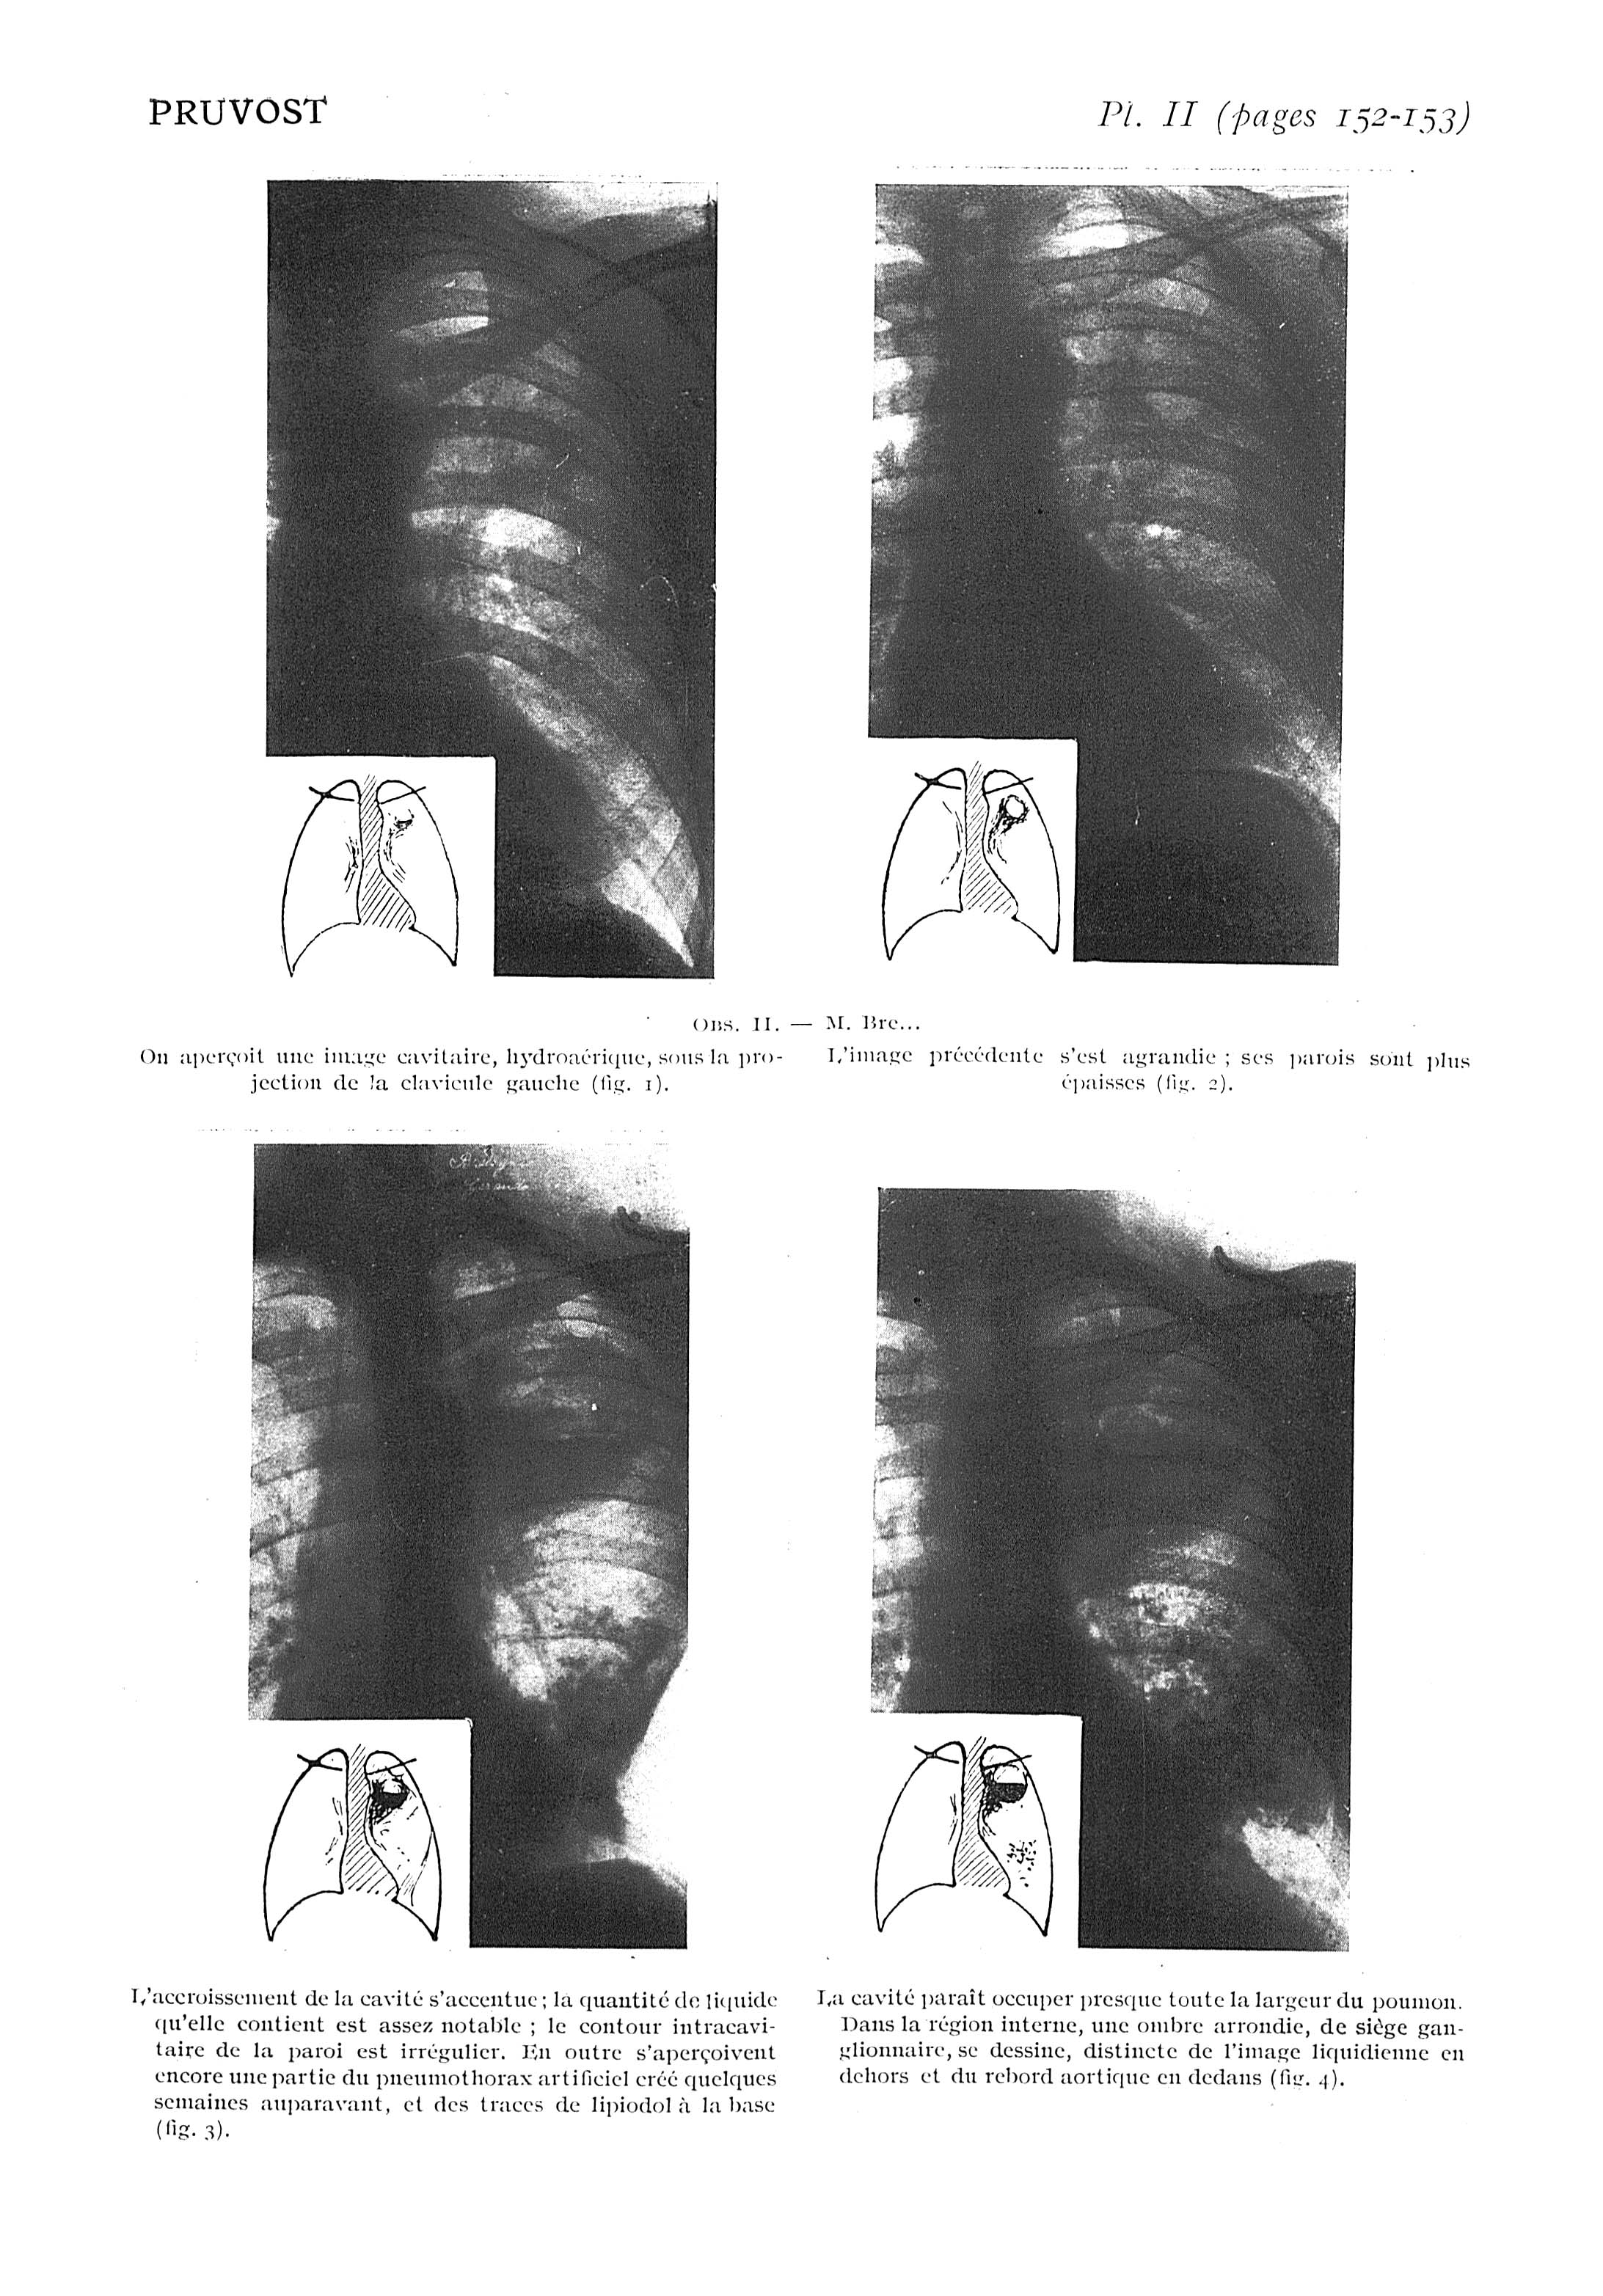

Fig. 1. - On aperçoit une image cavitaire, hydroaérique, sous la projection de la clavicule gauche / Fig. 2. - L'image précédente s'est agrandie ; ses parois sont plus épaisses / Fig. 3. - L'accroissement de la cavité s'accentue ; la quantité de liquide qu'elle contient est assez notable ; le contour intracavitaire de la paroi est irrégulier / Fig. 4. - La cavité paraît occuper presque toute la largeur du poumon - Paris médical : la semaine du clinicien